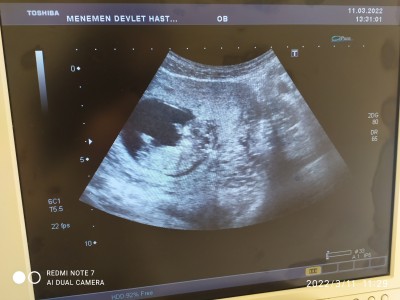

Keseden cinsiyet tahmini yapılıyormuş. Anlayan varsa tahminlerinizi yazabilir misiniz şimdiden herkese teşekkürler

Gebelik haftası 11+6